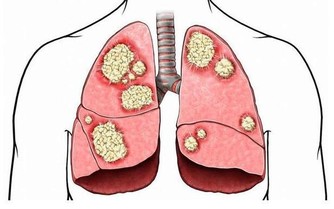

超重或肥胖者體內堆積太多脂肪,脂肪在肝臟中完成代謝,超出肝臟所承受的範圍,剩下的脂肪勢必會在肝細胞周圍堆積,從而導致肝細胞不能從血液中攝取營養,這裡面的代謝廢物也排不出體外,從而誘發脂肪肝。單純性脂肪肝並不可怕,適當地做好生活調理即可,但一直我行我素會逐漸發展成脂肪性肝炎,最終過渡到肝硬化或肝癌階段。因此應控制體重,從增加運動量和飲食方面入手,必要時還需借助醫學來減肥。

夏季天氣不僅炎熱而且濕度大,食物儲存不當或儲存時間太長,易滋生黃曲霉毒素,其毒性很強,也有一定的致癌性,攝入過量可增加患肝硬化或肝癌等風險,飲食飲食方面不能太節儉。若食物表面顏色發生改變、有異味等應立即扔掉。